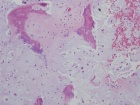

Patient is a 26 y/o male w/ hx. of polyostotic fibrous dysplasia s/p IM nailing for a pathologic L. femur fx. seven yrs. ago presents c/o 1 yr. hx. of increasing L. lat knee pain/swelling; PMH: polyostotic fibrous dysplasia and L. humerus fx; PE: L. knee w/ minimal effusion; +TTP over lat. condyle and w/ flexion to 100 deg; NVI